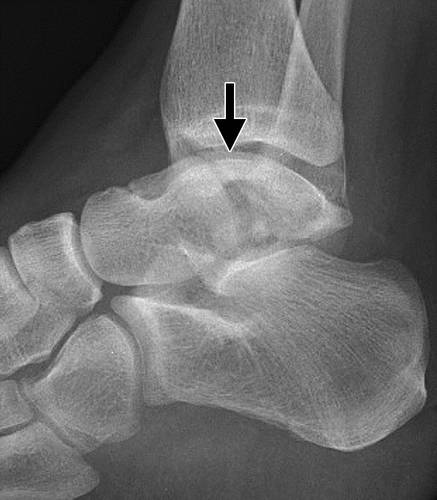

这种损伤必须与三角骨 - 一个附件后骨小梁区分开来。 在放射照相术中,后过程的断裂显示不规则的边缘(图13),而三角骨是圆形或椭圆形,具有光滑的皮质边缘(图14)。 双侧X线照片的价值有限,因为据报道三分之二的病例是双侧的(32)。 如果射线照片不确定,应进行CT。

图14 三角骨。 踝部的侧面X线片显示在距骨后方的椭圆形皮质骨化(箭头)。